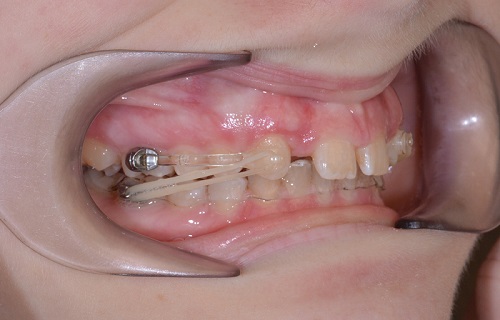

Jumping aparát

Aparát, který se uchycuje na fixní rovnátka jednostranně nebo i oboustranně. Používá se k léčbě výrazného předkusu a asymetrií skusu. Neomezuje otvírání úst. Na obrázku vypadá hrůzostrašně, ale ve skutečnosti nepůsobí větší problémy. Navíc je navenek jen velmi málo viditelný. V ústech bývá 4-6 měsíců. Tento aparát jsme již nahradili aparátem Carriere Motion.